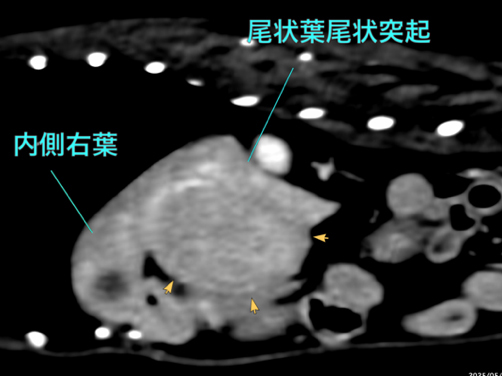

他院にて肝酵素の上昇および肝臓の結節性病変を指摘され、精査および治療のため当院に紹介来院となりました。右肝区域(W39 x L45 x H30mm)、尾状葉乳頭突起(W11 x L16 x H13mm)、内側左葉吻側領域、内側/外側左葉では、結節/腫瘤様の所見を複数認められ最大は外側左葉領域に40mm大の腫瘤が認められました。 本症例は、肝臓内の複数箇所に腫瘤性病変を有し、かつ高齢であることから、全身状態への負担を考慮し、右側および左側に対して2回に分けて肝動脈塞栓術を実施する方針としました。初回の処置として、右肝区域の腫瘤に対する動脈塞栓術を実施し、術後は大きな合併症もなく経過し、術後2日目に退院となりました。

手術前のCT検査での評価